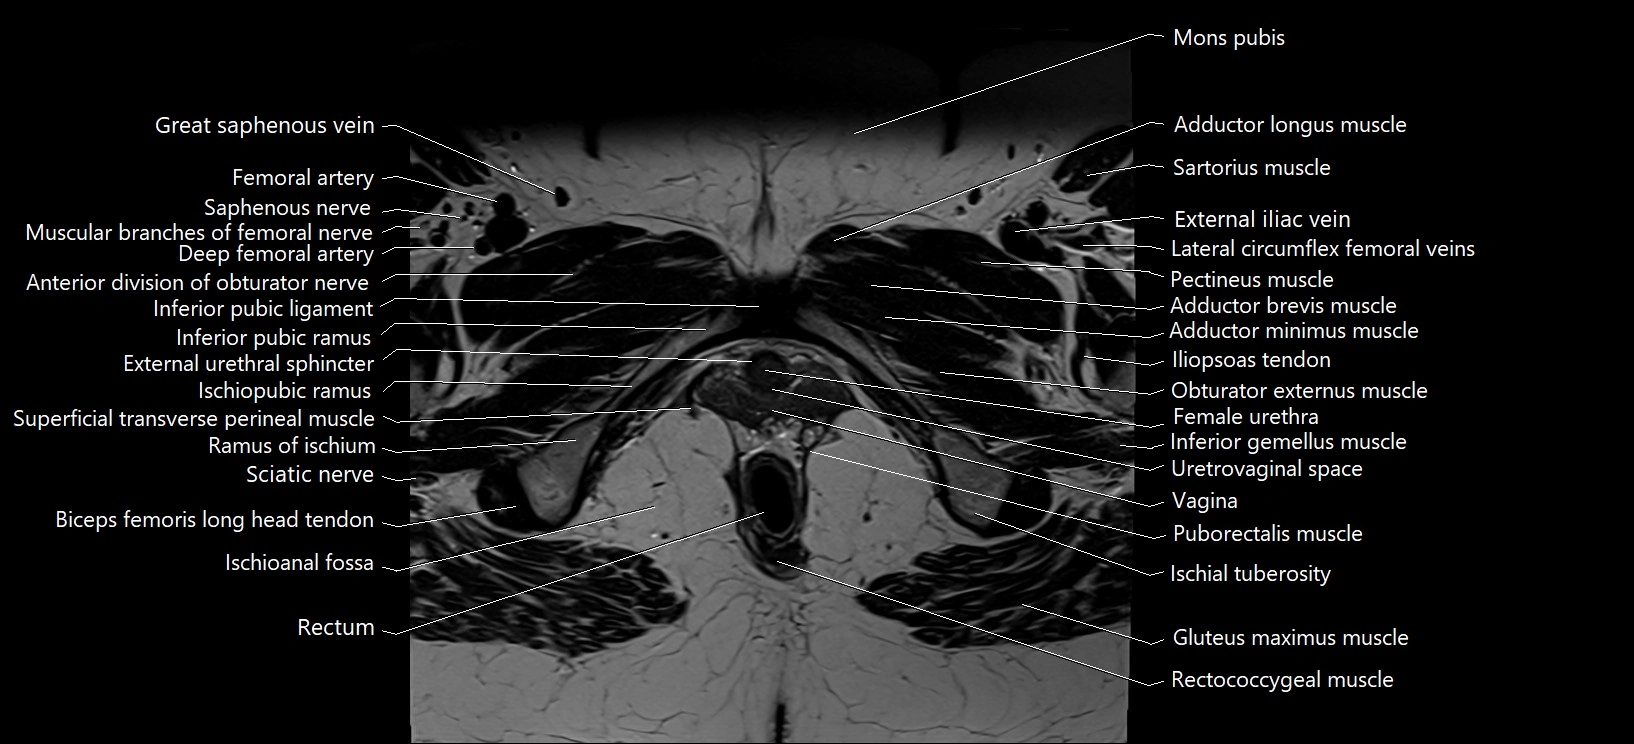

- External anal sphincter

- External urethral sphincter (female)

- Female urethra

- Gracilis muscle

- Inferior pubic ligament

- Inferior pubic ramus

- Ischioanal fossa

- Mons pubis

- Muscular branches of femoral nerve

- Puboanalis muscle

- Puborectalis muscle

- Rectococcygeal muscle

- Rectum

- Sciatic nerve

- Superficial transverse perineal muscle

- Vagina